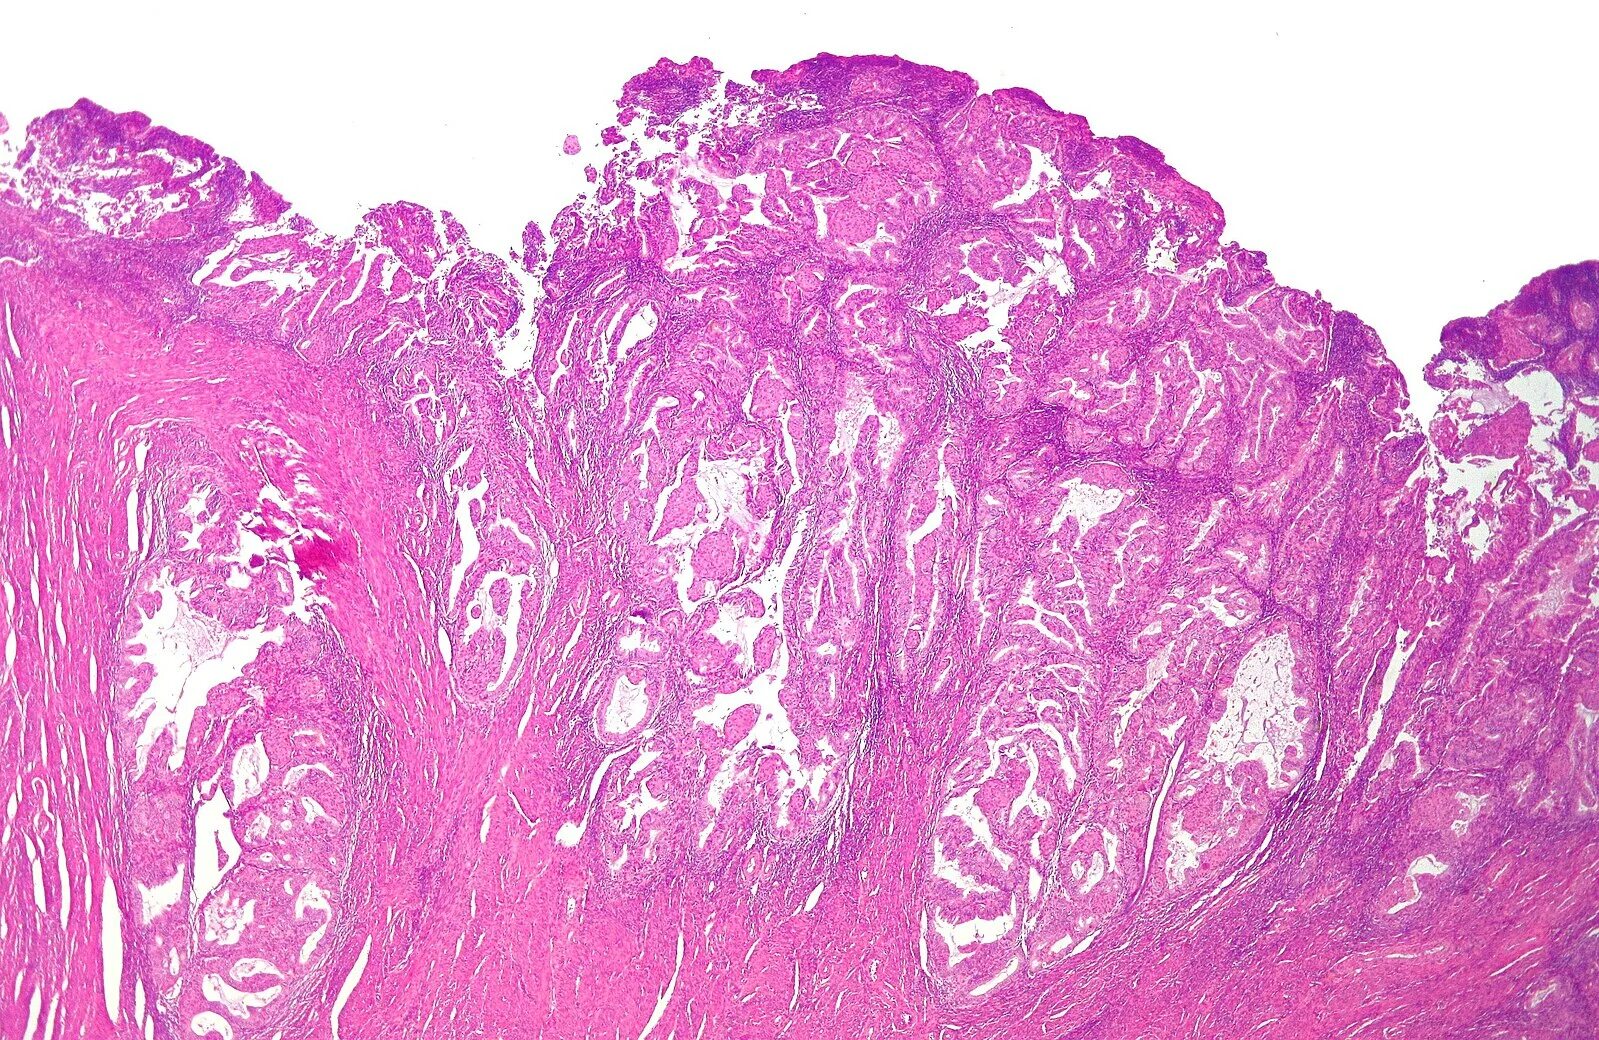

Эндометрит гистология